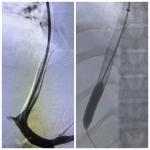

تضمن اليوم تدريب الأطباء على كيفية إجراء منظار المعدة، ومنظار قولون، ومنظار ربط دوالي، ومنظار كي أرجون، ومنظار توسيع مرئ، كما تم تدريبهم على إجراء منظار قنوات مرارية تضمن تركيب دعامة معدنية و استخراج حصوة كبيرة بالقناة المرارية، وكذلك التدريب على إجراء منظار موجات فوق صوتية تضمن تفريغ كيس كبير نتيجة عيب خلقي بالإثنى عشر، وتم تقييم ورم بالبنكرياس.

The workshops included training doctors on how to perform gastroscopy, colonoscopy, esophageal variceal ligation, ERCP, and esophageal dilation. They were also trained on how to perform biliary endoscopy including inserting a metal stent and extracting a large stone from the bile duct, as well as training on how to perform endoscopic ultrasound including draining a large cyst due to a congenital defect in the duodenum and evaluating a pancreatic tumor.